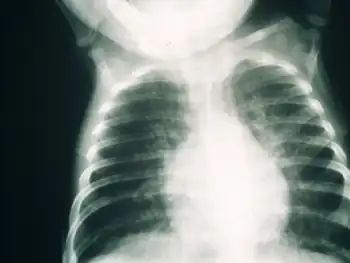

Infant with severe combined immunodeficiency showing bilateral patchy shadowing secondary to interstitial pnuemonitis

Early diagnosis of SCID is usually difficult due to the need for advanced screening techniques. Several symptoms may indicate a possibility of SCID in a child, such as a family history of infant death, chronic coughs, hyperinflated lungs, and persistent infections. A full blood lymphocyte count is often considered a reliable manner of diagnosing SCID, but higher lymphocyte counts in childhood may influence results. Clinical diagnosis based on genetic defects is also a possible diagnostic procedure that has been implemented in the UK.[12]